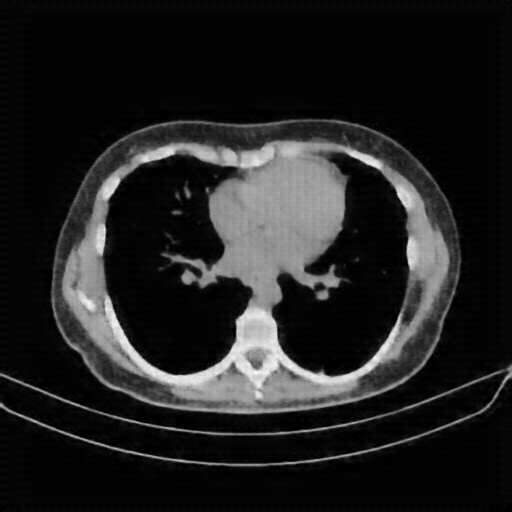

Image Grid

4Γ—3 grid: Rows show different image types (Original NATIVE, Reconstructed NATIVE, Original VENOUS, Generated VENOUS), Columns show windowing techniques (No Window, Lung Window, Mediastinum Window)

Original VENOUS CT scan

Full window (WL 1023.5, WW 4095 β†’ Low βˆ’1024, High +3071)

Lung window (WL -600, WW 1500 β†’ Low βˆ’1350, High +150)